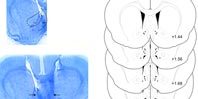

Разобраться в этом вопросе ученые попытались, исследовав мозг мышей. Оказалось, тетрагидроканнабинол (основной психоактивный компонент марихуаны) производил положительный эффект только в прилежащем ядре, и исключительно в передних областях. Сильные негативные эффекты также наблюдались в зоне прилежащего ядра, но в других областях. Среди них были когнитивные и эмоциональные симптомы, связанные с шизофренией.

По словам ученых, различный эффект наркотика можно объяснить генетическими вариациями, которые приводят к разной чувствительности каждой зоны мозга. Считается, положительный или отрицательный эффект зависит от того, какая часть прилежащего ядра наиболее чувствительна к тетрагидроканнабинолу.